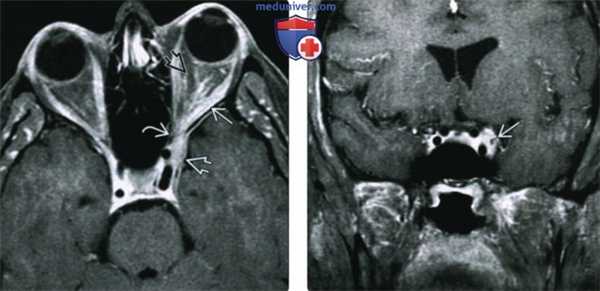

(Слева) При MPT Т1ВИ FS с КУ в аксиальной проекции определяется обширный контрастный идиопатический воспалительный псевдотумор, инфильтрирующий верхушку глазницы, решетчатый лабиринт и круглое отверстие.

(Справа) При МРТ T1ВИ с КУ в аксиальной проекции (срез проходит ниже) у этого же пациента определяется двусторонний псевдотумор крылонебной ямки, непосредственно соединенный с идиопатическим воспалительным псевдотумором полости носа. Также поражены обе нижние глазничные щели. Обширные идиопатические воспалительные псевдотуморы глаз-ниц/внеглазничной локализации зачастую трудно поддаются лечению стероидами.

(Слева) МРТ, постконтрастное Т1-ВИ, режим подавления сигнала от жира, аксиальный срез: визуализируется протяженная накапливающая контраст зона инфильтрации верхушки глазницы S3, решетчатой пазухи и круглого отверстия, представляющая собой идиопатический воспалительный процесс.

(Справа) МРТ, постконтрастное Т1 -ВИ, режим подавления сигнала от жира, более каудальный аксиальный срез: у этого же пациента наблюдается двустороннее вовлечение в процесс крылонебных ямок в сочетании со смежным инртраназальным ИВВ. Также отмечается вовлечение в процесс обеих нижних глазничных щелей. Протяженные зоны ИВГл-ИВВ часто плохо реагируют на стероидную терапию.